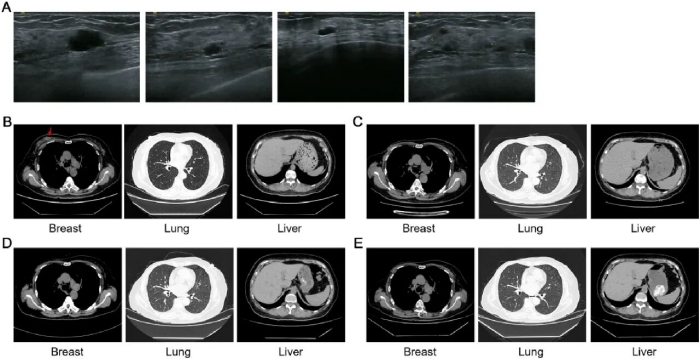

▲ 患者的影像检查。(A)代表性彩超右胸图片。(B-E)2021年6月22日(B)、2022年6月6日(C)、2023年7月20日(D)和2024年7月19日(E)分别拍摄的乳腺、肺部和肝脏CT图像。